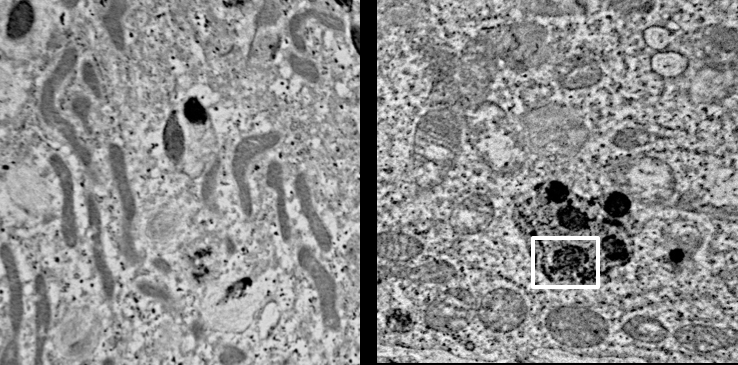

Important to the execution of this project and highlighting the role of CLN3 in hiPSC-derived retinal cell model, 1) robust expression of CLN3 protein is observed in hiPSC-derived retinal cells from control (unaffected subjects) (see image below) and 2) JNCL-patient-derived hiPSC-retinal cells display important pathological manifestations of the disease including increased autofluorescent material accumulation and presence of fingerprint inclusions within the cells, the two phenotypic hallmarks of the human disease.

Representative confocal microscopy images showing increased autofluorescence accumulation in JNCL patient-derived hiPSC-optic vesicles compared to control hiPSC-optic vesicle (left) and typical fingerprint inclusions (highlighted within a box) in JNCL patient vs. control hiPSC-retinal pigment epithelium or RPE (right).